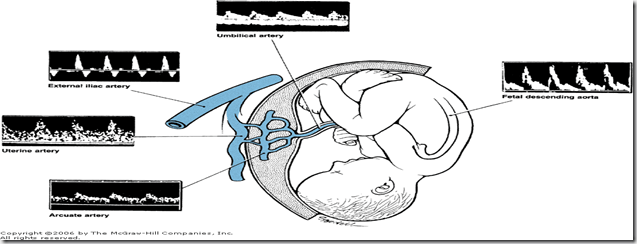

The Doppler equation shown in Figure 16–17 contains the variables that affect the Doppler shift. An important source of error when calculating flow or velocity is the angle between sound waves from the transducer and flow within the vessel—termed the angle of insonation and abbreviated as theta (). Because cosine  is a component of the equation, measurement error becomes large when the angle of insonation is not close to zero. The practical solution to this problem has been the use of ratios to compare different waveform components—allowing cosine  to cancel out of the equation. Figure 16–18 is a schematic of the Doppler waveform and describes the three ratios commonly used. The simplest is the systolic–diastolic ratio (S/D ratio), which compares maximum (peak) systolic flow with end-diastolic flow, thereby evaluating downstream impedance to flow.

image

Doppler waveforms from normal pregnancy. Shown clockwise are normal waveforms from the maternal arcuate, uterine, and external iliac arteries, and from the fetal umbilical artery and descending aorta. Reversed end-diastolic flow velocity is apparent in the external iliac artery, whereas continuous diastolic flow characterizes the uterine and arcuate vessels. Finally, note the greatly diminished end-diastolic flow in the fetal descending aorta. (From Copel and colleagues, 1988.)